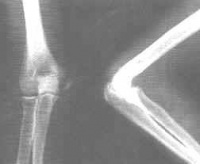

X线照片,可明确诊断。

5岁-7岁以上的儿童肱骨内上髁骨骺已经骨化,肱骨内上髁骨骺分离X线表现为点状骨骺与肱骨远端分离较远,可并有向下移位,局部软组织肿胀。

成年人的肱骨内上髁骨折,损伤程度差异很大。可为整个肱骨内上髁骨折,亦可仅为少量撕脱骨片。